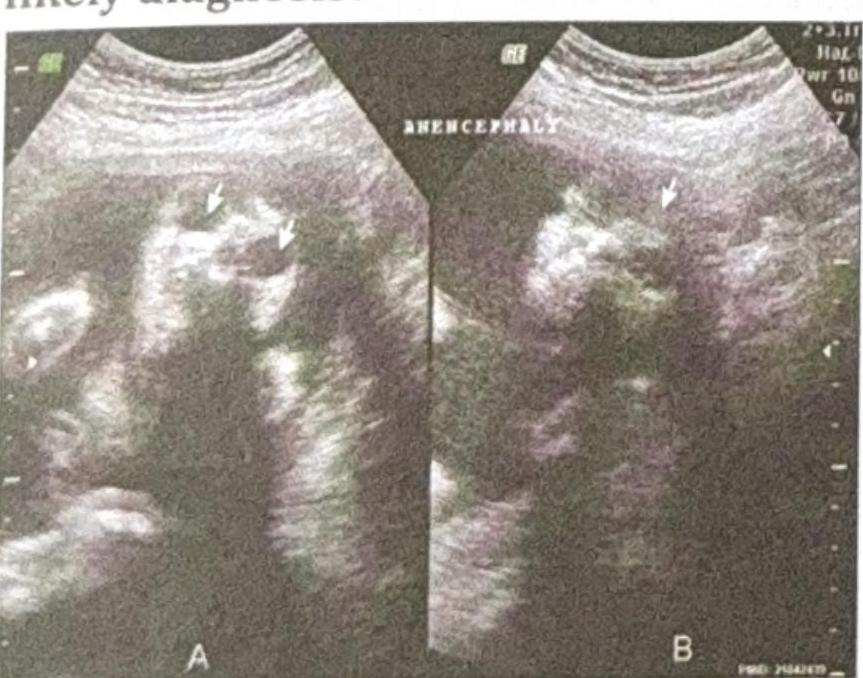

A 25-year-old pregnant woman, at 18 weeks of gestation, undergoes a routine ultrasound scan. The ultrasound images provided show below. Based on the imaging findings, what is the most likely diagnosis?